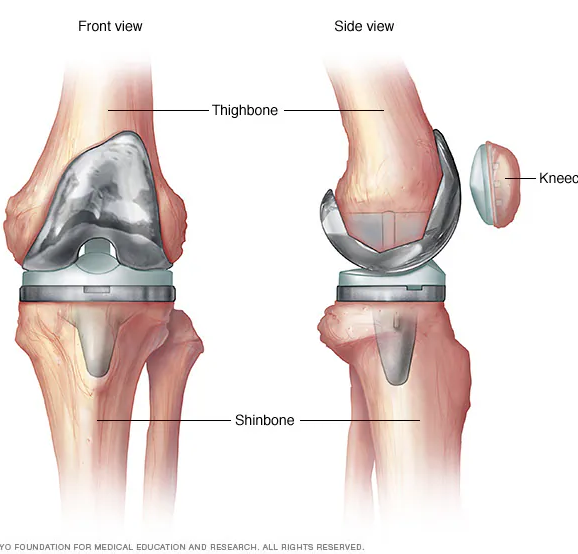

Knee Arthritis

Knee Preservation

Total Knee Replacement (TKR) Package – Implant Based Cost Guide